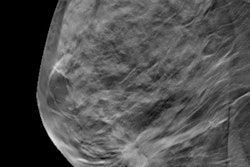

ICE Reveal features algorithms designed to transform grayscale images such as mammograms into more clearly defined, visually apparent, and qualitatively distinct patterns. The Mayo Clinic will spearhead Imago's pilot and pivotal studies to clinically validate the visual intelligence software as applied to screening mammograms, the company said.